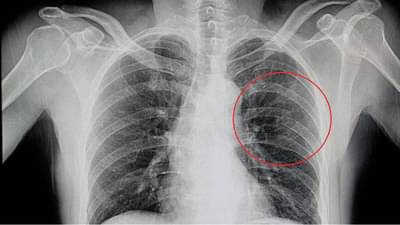

या समस्येबाबत महिला जवळच्या डॉक्टरांकडे गेली असता, तिला सीटी स्कॅन करून घेण्यास सांगण्यात आले. हा अहवाल पाहिल्यानंतर डॉक्टरांनी तिला सांगितले की, हुआंगच्या बरगड्या तुटल्या आहेत आणि तिला एक महिना कंबरेवर पट्टी बांधणे आवश्यक आहे.